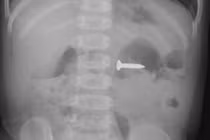

| Mảnh xương được lấy ra từ mũi của bệnh nhân. Ảnh BVCC |

Theo các bác sĩ, đây là trường hợp rất hiếm gặp, dị vật là mảnh xương có cạnh sắc nhọn mắc trong mũi người bệnh.